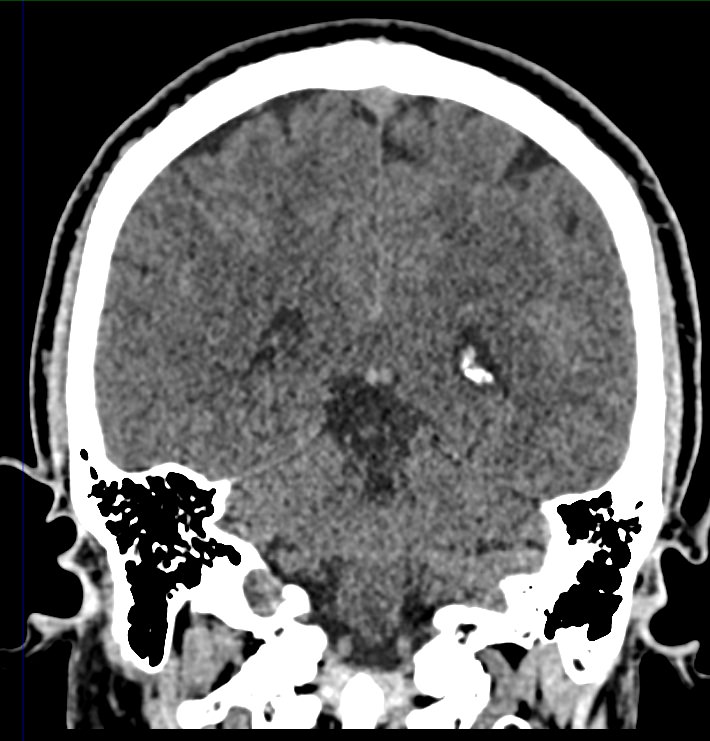

Мультиспиральная компьютерная томография головного мозга относится к лучевым методам диагностики заболеваний центральной нервной системы.

Методика построена на использовании проникающей способности рентгеновских лучей, которые в различной степени поглощаются органами и тканями (степень поглощения зависит от их плотности), благодаря чему можно получить подробные изображения внутренних органов. Во время исследования трубка томографа вращается вокруг пациента и производит снимки поперечного сечения, что позволяет детально визуализировать кости черепа и все структуры головного мозга.

Наши медицинские центры оснащены новейшими мультиспиральными компьютерными томографами экспертного уровня TOSHIBA AQUILION в различных модификациях. Аппараты снабжены увеличенным количеством сверхчувствительных детекторов, что позволяет при сканировании выполнять от 64 до 128 срезов поперечного сечения с минимальной толщиной среза от 0,5 мм. В результате получаются изображения исследуемой зоны в мельчайших подробностях, которые затем с помощью инновационных цифровых приложений преобразуются в трехмерные пространственные модели головного мозга для более точной диагностики.

Нативное сканирование подходит для диагностики дистрофических изменений головного мозга, определение острого нарушения мозгового кровообращения, как ишемического, так и геморрагического характера, а также отслеживание последствий подобных состояний при прохождении реабилитации.

Для улучшения видимости внутричерепных структур применяется методика внутривенного болюсного контрастирования. Во время проведения КТ пациенту в вену вводится йодсодержащее контрастное вещество. Контраст с током крови попадает в патологически измененные участки ткани и очаги, что на снимках придает им яркие отличительные признаки по сравнению с окружающими здоровыми тканями. Контрастирование, в первую очередь, помогает в диагностике опухолевых процессов на ранних стадиях, когда лечение может дать наилучший эффект.

Что можно выявить на КТ головного мозга?

- нарушения мозгового кровообращения (имеются в виду как геморрагические, так и ишемические инсульты);

- другие сосудистые патологии в области головного мозга (аневризмы, артерио-венозные мальформации и пр);

- мелкоочаговые кровоизлияния, гематомы;